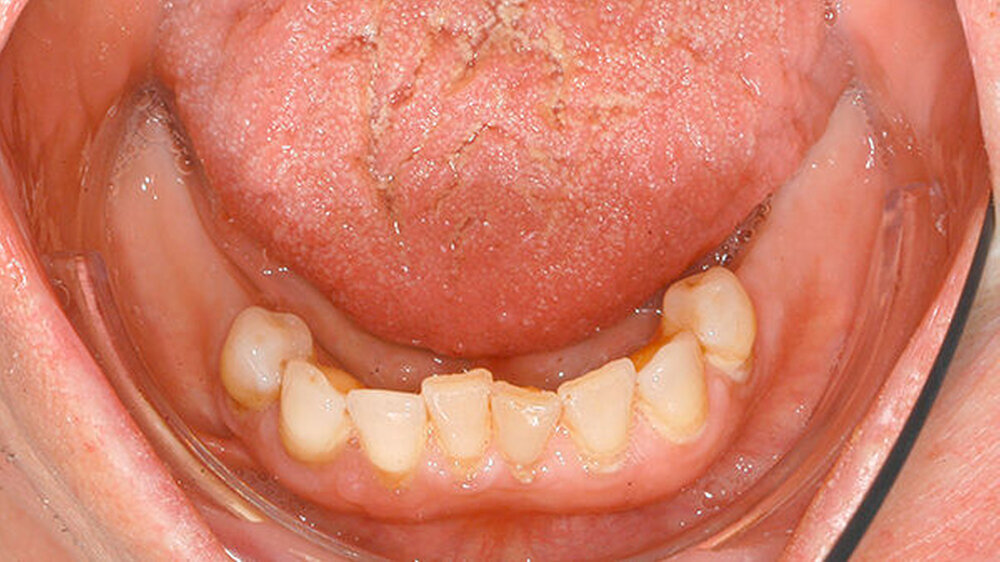

Bei der intraoralen Inspektion zeigte sich eine deutlich hyperplastische Gingiva mit Blutung auf Sondieren (BOP) (Abbildung 1). Da der Patientin die Handhabung einer Zahnbürste schwerfällt, zeigten sich auch deutliche Plaqueanlagerungen.

Aufgrund der schmerzhaften Gingivitis hatte die Patientin zudem Probleme mit der Nahrungsaufnahme. In der Panoramaschichtaufnahme (Abbildung 2) zeigt sich neben einem impaktierten Eckzahn ein Furkationsbefall der Molaren mit Konkrementen sowie ein altersentsprechender, generalisierter horizontaler Knochenabbau. Dennoch erschien uns das Volumen der Gingiva nach bereits erfolgter geschlossener Parodontaltherapie ungewöhnlich.